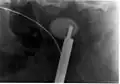

Hvězdovitě tvarovaný kámen v měchýři na RTG pánve. -